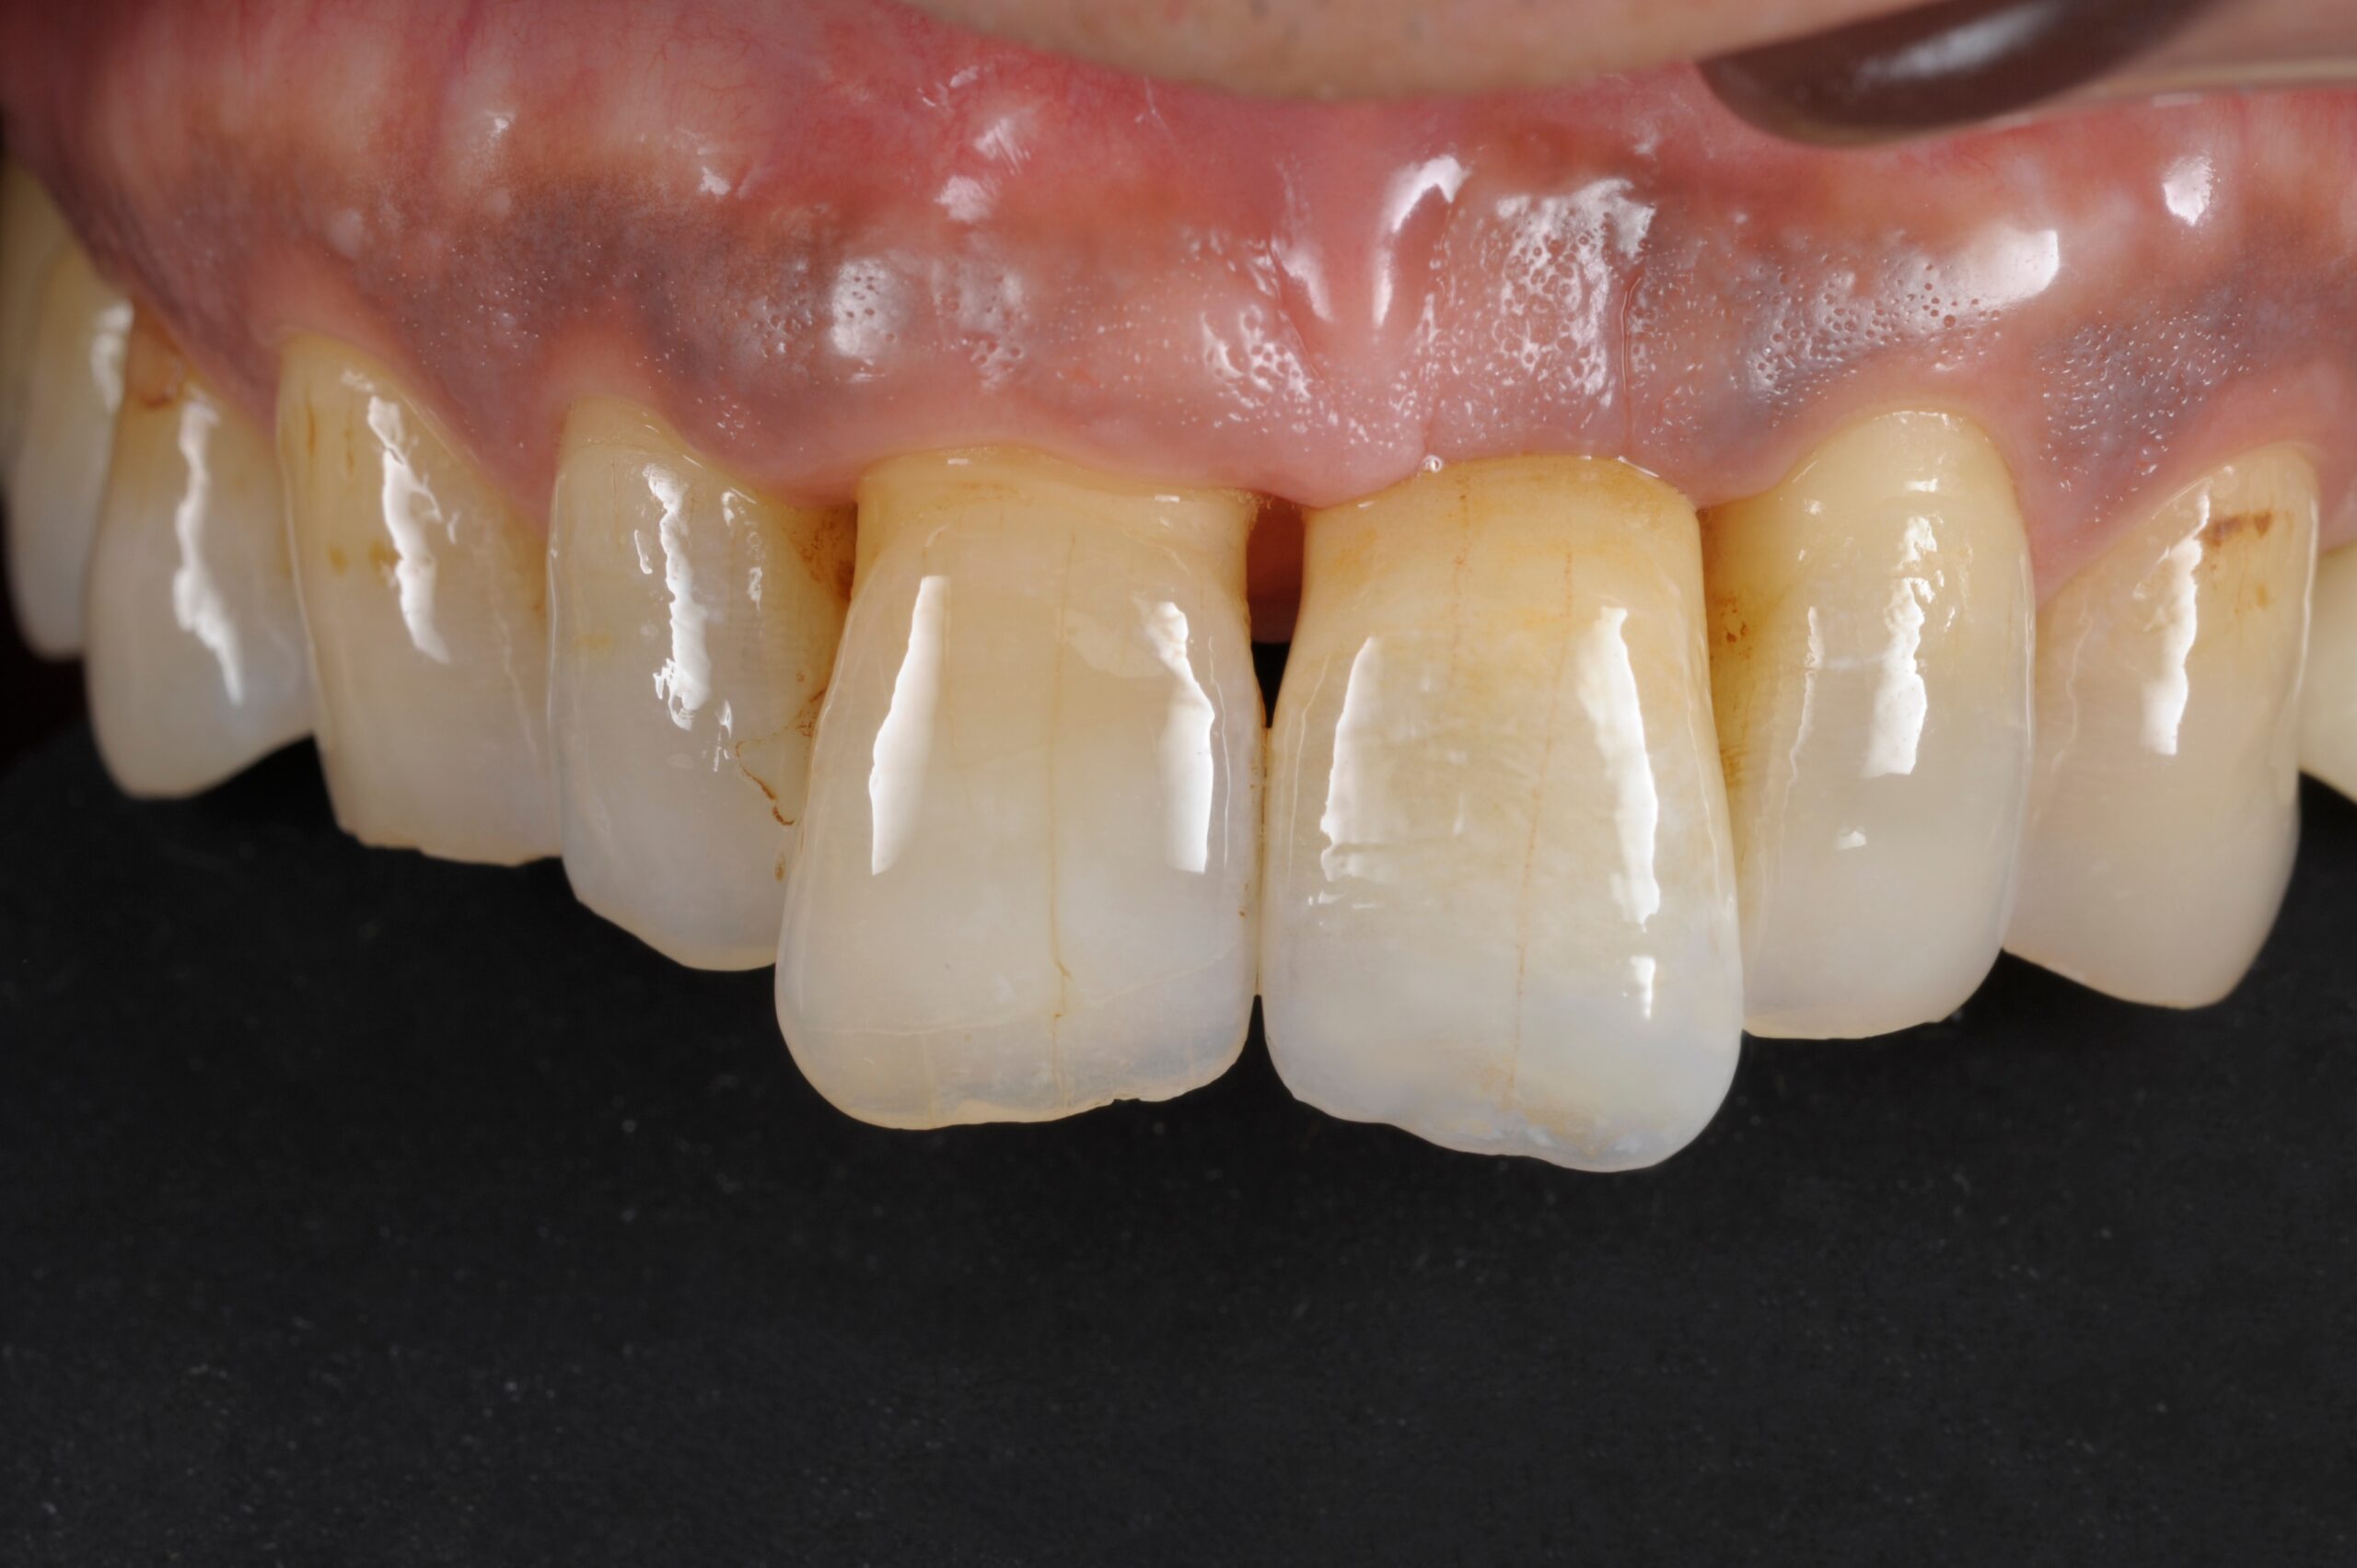

前歯インプラント症例

主訴 歯を入れたい(男性) 治療内容 1本インプラントの一般的な治療過程です。 プラマRFインプラントを埋入。

手術後3ヶ月待ち、骨とインプラントが固まったことを確認し、二次手術後に型取りを行っています。当院では、ほとんどの症例でデジタルでの型取りを行っています。

インプラントを埋入した部位に型取り用のパーツをはめ、3Dスキャナーにて型取りをし、ジルコニアクラウンの被せ物を作製しています。ご自身の歯と変わらないような仕上がりとなっています。

治療期間 約6ヶ月 費用 総額 ¥350,000-(税別) リスクと副作用 ・外科治療となるので、お身体の状態によっては受けれない場合がある(広範囲に適用可能な治療ですが、個々の患者様の状況によって適用外な場合もある)

・術後に多少の痛みや腫れが出ることがある